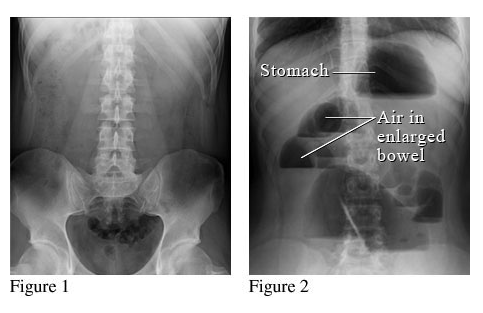

Bác sỹ có thể tiến hành chụp CT hay chụp X quang ổ bụng để tìm ra chính xác vị trí tắc và nguyên nhân gây bệnh. Nếu tắc tại ruột già, bác sỹ sẽ tiến hành nội soi hoặc chụp cản quang để quan sát ruột.